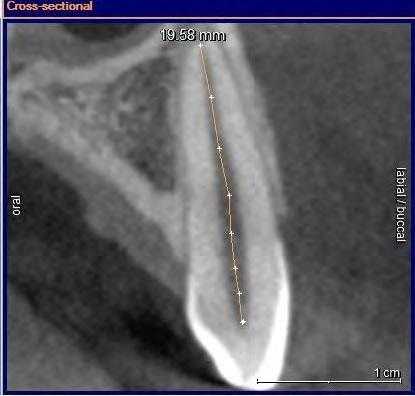

С изобретением нового программного обеспечения для КЛКТ Orthophps CG3D/Galelios (Sirona, Germany) рабочая длина каналов также стала осуществляема. Но точность этих данных в клинической работе еще должна быть подтверждена (Фото 3).

Фото 3: Инструмент для измерения длинны корневого канала